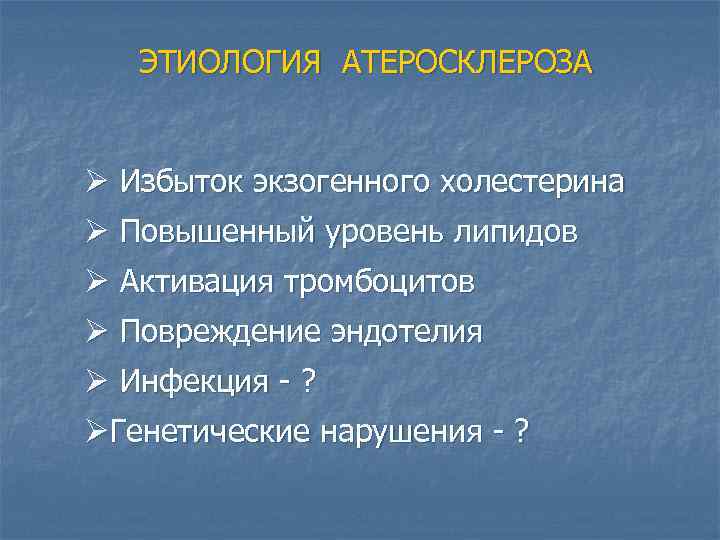

ЭТИОЛОГИЯ АТЕРОСКЛЕРОЗА Ø Избыток экзогенного холестерина Ø Повышенный уровень липидов Ø Активация тромбоцитов Ø Повреждение эндотелия Ø Инфекция - ? ØГенетические нарушения - ?